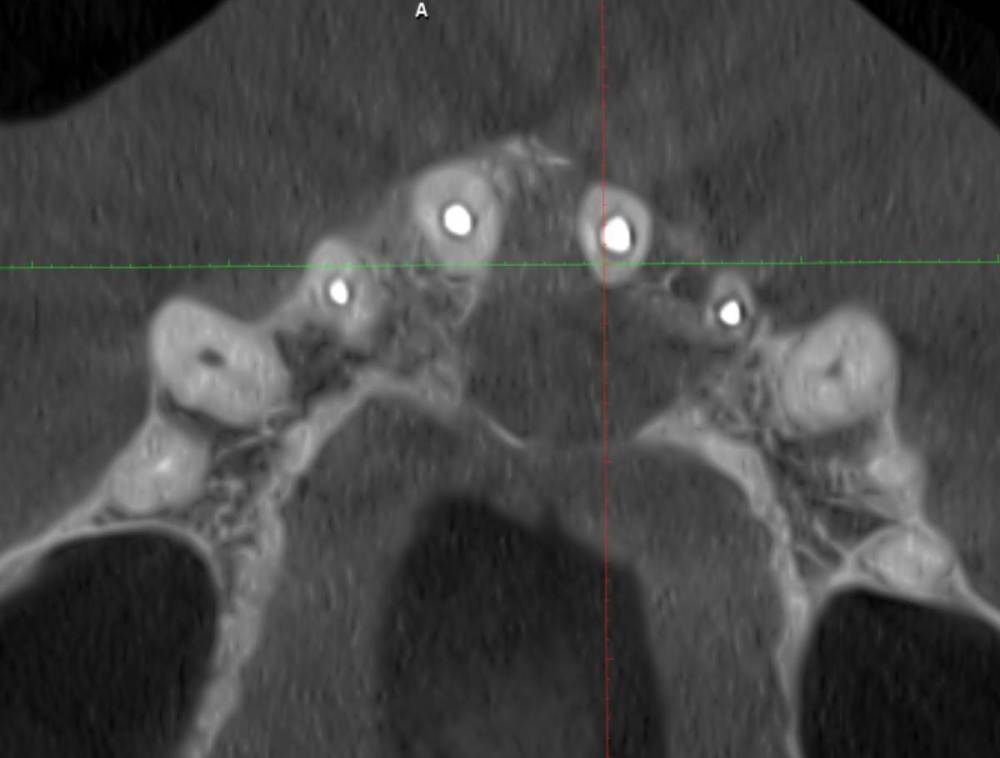

feGTX Опубликовано 15 июля, 2022 Поделиться Опубликовано 15 июля, 2022 (изменено) Здравствуйте. Очень нужна помощь стоматологов! В 2019 году обнаружил свищ над верхними передними зубами. Пошел к своему стоматологу, который начал следующее лечение: - нервы в зубах были удалены и пару дней я ходил с открытым каналом. Далее закладывался Метапекс, а потом постоянная пломба, но свищ не закрылся. 22 зуб также залечили. Были консультации и в других стоматологиях нашего маленького городка (КТ тогда тоже делалось), но в основном рекомендовали три зуба под удаление, закладывание искусственной кости, импланты или мосты на соседние зубы. Решили пробовать перелечивать со своим стоматологом. - 21 зуб снова вскрыли и несколько раз закладывали Кальцетин. Потом снова постоянная пломба. И свищ закрылся (это было осенью 2019 года). Далее делали несколько снимков - вроде медленно шло заживление. В сентябре 2021 года делал КТ нижней челюсти по другой проблеме, и захватилась верхняя челюсть - тоже были видны улучшения в сравнении с самой первой КТ. И вот на днях снова свищ на десне. Надавливаю под носом и выходит жидкость. Снимок сделали, но как-то коряво вышел он. Сделал также КТ. Снова всё плохо. Во вложении три старых снимка, один свежий, и несколько изображений с КТ. Если нужны еще какие-то срезы, то попробую сделать. Помогите пожалуйста. Изменено 15 июля, 2022 пользователем feGTX Ссылка на комментарий